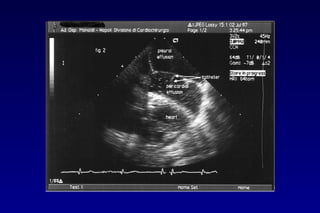

METODOLOGIA DI STUDIO DEL VERSAMENTO

PERICARDICO

• L’accumulo patologico

di fluido determina la

separazione sisto-

diastolica tra i due

foglietti con comparsa

di un’immagine a

doppio contorno che

racchiude uno spazio

relativamente privo di

echi

Linfoma mediastinico

Valutazione quantitativa? CT?

Valutazione quantitativa?

ETE?

Utile nello studio di versamenti pericardici saccati.